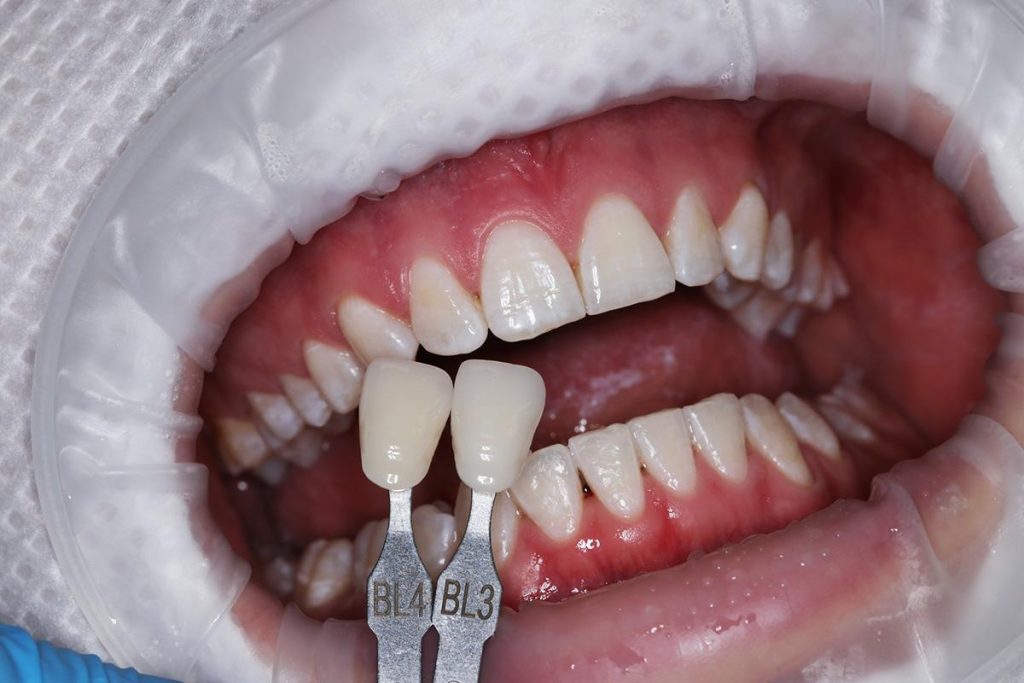

- Przeprowadziliśmy wybielanie zębów, aby uzyskać idealny odcień.

- Wykonaliśmy pełnoceramiczne licówki na górne jedynki.

- Zmieniliśmy wygląd kła przy pomocy licówki, aby wyglądał jak naturalna dwójka.